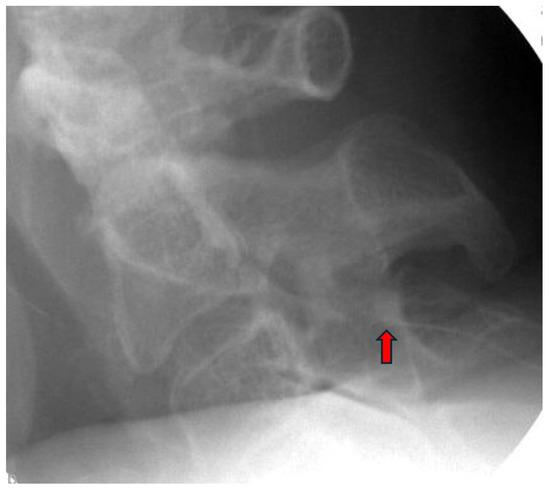

3.3. Procedure Description